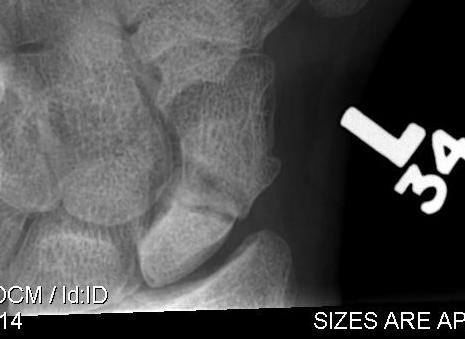

AVN

Osteonecrosis of the navicular

Xray

- sclerosis

CT